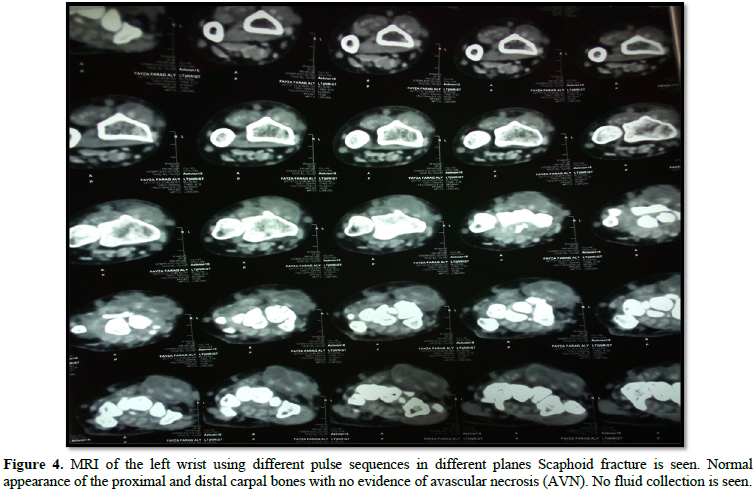

Tuberculosis of the wrist is an uncommon clinical entity and mostly presents as insidious pain and swelling. Presentation of a singular carpal bone involvement as the sole feature of tuberculous infection is a relatively uncommon event. In this report the authors describe a case of scaphoid fracture in a 20‑year‑old male patient, and underlying tuberculous infection suspected by ultrasonographic examination of the wrist joint, magnetic resonance imaging and guided aspiration and culture of the joint fluid. Introducing anti tuberculous drugs under appropriate supervision resulted in clinical improvement and optimal regain of function. No reactivation of the disease was noted in a follow‑up of 2 years. This case highlights a rare presentation of tuberculosis presenting with a fracture of scaphoid.